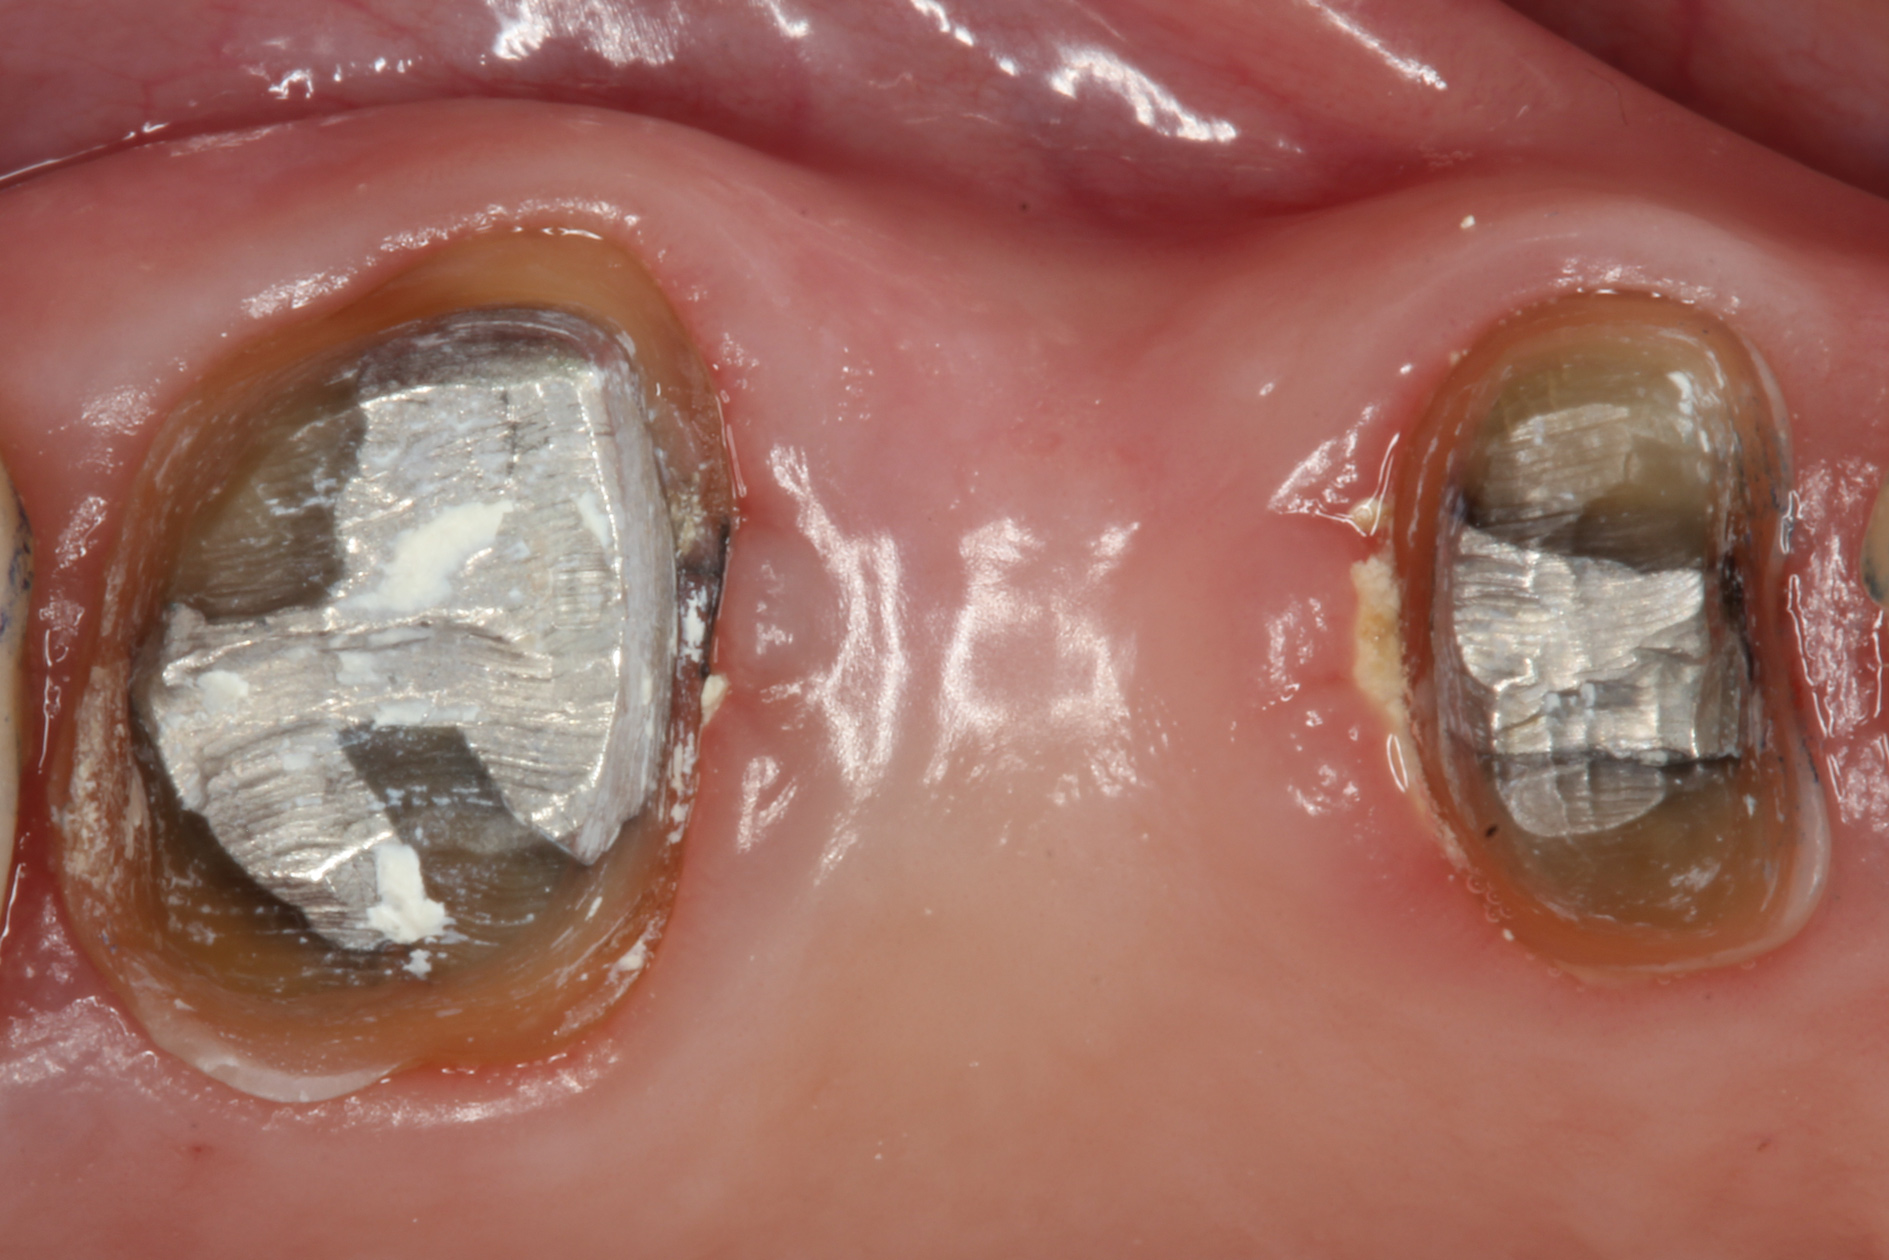

Fig 13. Crown preparations with temporary cement remnants prior to air abrasion (Fig 13) and after air abrasion (Fig 14) (case by Mohammed Badahman, DDS).

Figure 13

Fig 14. Crown preparations with temporary cement remnants prior to air abrasion (Fig 13) and after air abrasion (Fig 14) (case by Mohammed Badahman, DDS).

Figure 14

With these limitations acknowledged, visual inspection of tooth preparations after air abrasion reveals that this modality is effective in removing remnant restorative materials, stains, and temporary cement, leaving a clean, matte surface for bonding (Figure 11 through Figure 14). Air abrasion also can smooth the internal aspects of a cavity preparation to help enable better adaptation of the restorative material (Figure 15 and Figure 16). The technique-sensitive nature of adhesive bonding may justify this extra procedure to ensure a clean, smooth preparation.